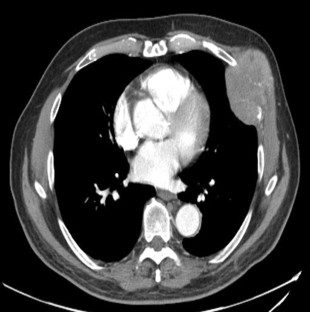

Fig. 2